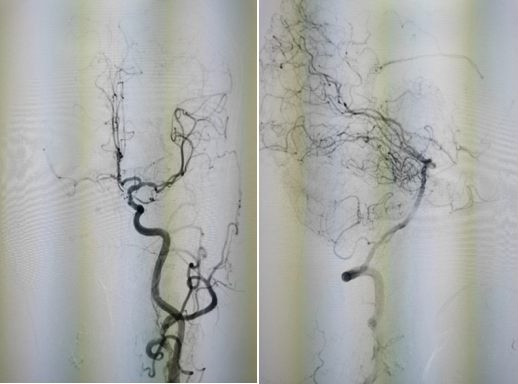

图4 TOF像显示岩骨段慢血流

图5 眼段可见正常管腔,血管负性重构

图6 M1段血管存在